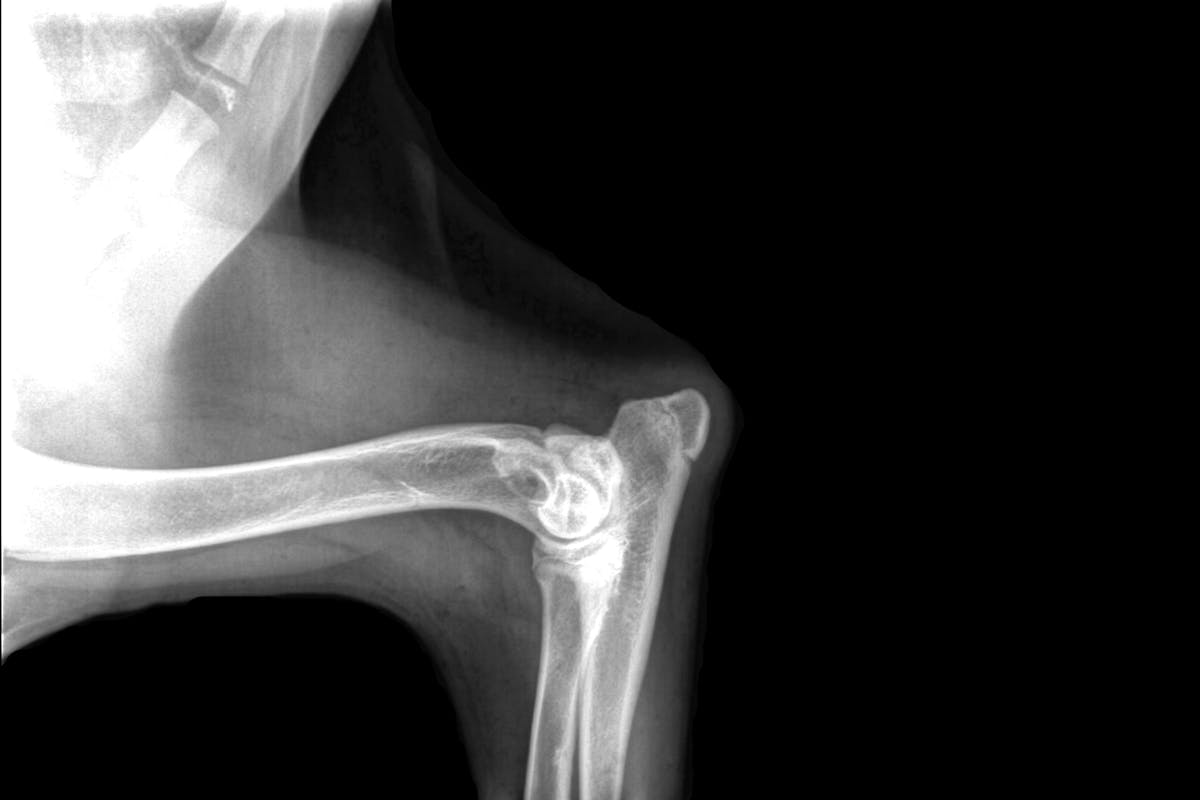

Elbow Dysplasia refers to abnormalities in the joint that can result in the breakdown of cartilage in the joint over time, resulting in varying degrees of pain and lameness over time.

Screening requires x-rays, performed by a licensed veterinarian, be submitted to OFA for review. Submitted radiographs are reviewed independently by 3 randomly selected board-certified veterinary radiologists.

Dogs must be at least 24 months of age to have elbows certified as normal by OFA. The OFA does offer a preliminary evaluation for those less than 24 months of age, but the predictive value of preliminary evaluation is unknown for elbow dysplasia.